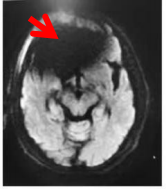

由于种植牙已固定在牙槽骨上或黏合在相应的连接物上,具有很高的牢固度,通常在3.0T(含) 以下场强的MRI设备中不会发生移动和变形,所以不用担心你的牙齿会被吸飞了哦,但在牙科植入物所在的部位可能会出现一些伪影。 像下图这样:

但是如有可拆卸的假牙或者金属牙箍,建议MRI检查时取下,不然影像可能会和下面图像一样,黑乎乎的一片,什么都看不见,这种情况就要影响诊断了。